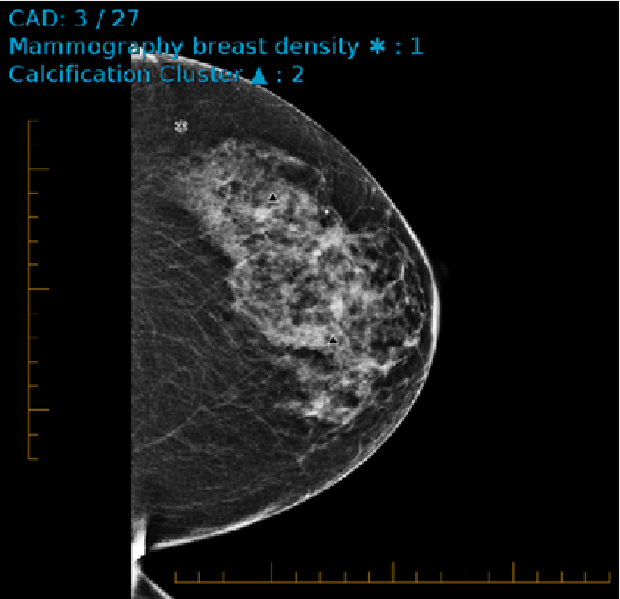

Displaying Genius AI CAD on 2D Images

In the following example, which is from the Genius AI CAD, three out of the twenty-seven CAD marks for the exam appear on this image. Depending on the count and type of CAD markings on the image, the number is displayed next to it’s associated icon in the image overlays.

The following CAD markings are visible on the image:

• The compass (+) icon indicates the Mass with calcifications.

• The triangle () icon indicates Calcification Cluster.

• The asterisk (*) icon indicates the Mammography breast density.

CAD marks appear automatically on images if indicated in the reading step when abnormalities are detected. You can override the CAD instructions in the reading step and show or hide CAD marks manually.